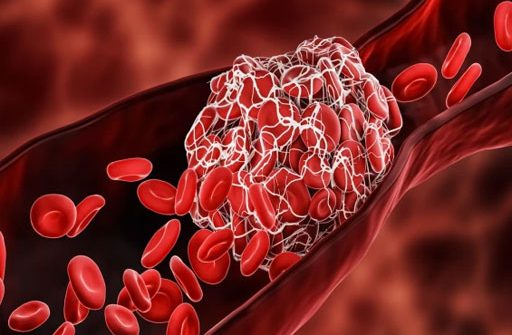

زیادہ تر انرجی ڈرنکس میں کیفین ایک بنیادی جزو کے طور پر شامل ہوتی ہے، جو توانائی بڑھانے اور چوکنا رکھنے کے لیے مشہور ہے۔ تاہم، طبی ماہرین کا کہنا ہے کہ کیفین جسم میں انسولین کی سطح کو متاثر کر سکتی ہے، جس کے نتیجے میں DHT (ڈائی ہائیڈروٹیسٹوسٹیرون) کی پیداوار میں اضافہ ہوتا ہے، جو براہ راست بالوں کے گرنے سے جڑا ہوا ہے۔